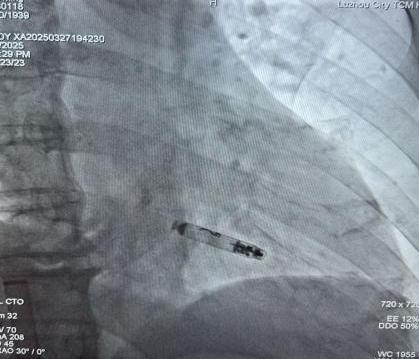

起搏器釋放后影像

劉大爺?shù)氖中g(shù)在朱彬帶領(lǐng)下實(shí)施,在局麻下進(jìn)行。通過股靜脈將約二分之一7號電池大小的無導(dǎo)線起搏器送入他的右心室,再利用獨(dú)有的螺旋錨定裝置牢牢地將其固定于心肌。術(shù)中、術(shù)后參數(shù)測試均良好,如今患者術(shù)后恢復(fù)良好,心臟逐漸恢復(fù)“活力”,未再出現(xiàn)過頭暈癥狀,術(shù)后隨訪提示預(yù)估壽命20-30年。